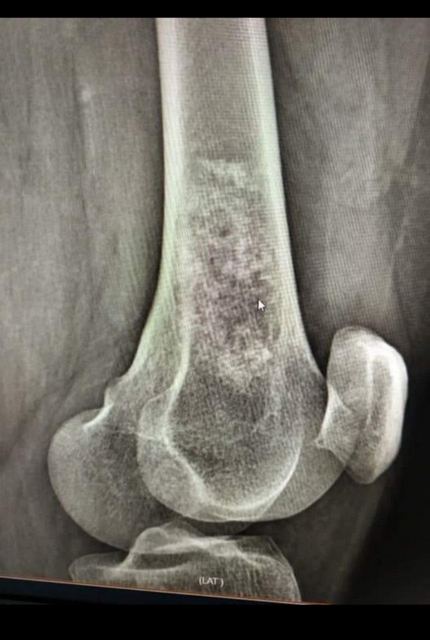

300 000 гривень – саме таку суму необхідно зібрати вже менше, ніж за два тижні, Олесі Кондратюк. Жінці лише 41 рік, вона працює маляркою. Нещодавно лікарі встановили їй страшний діагноз – «Міксоїдна хондросаркома н/3 лівої стегнової кістки». Це злоякісна пухлина, яка атакувала колінний суглоб.

Уже більше, ніж пів року, розповідає Олеся Кондратюк, вона страждає на біль у суглобі та кульгавість. Спершу вона не звертала на це уваги. А в січні жінка впала на коліно та дуже забилася. Тоді ж біль посилився, й оперативно довелося зробити рентген. Як наслідок, побачили пухлину. Уже після біопсії в Києві та Харкові виявилося, що вона злоякісна. Жінку направили в Інститут патології хребта та суглобів ім. професора М. Г. Ситенка НАМН «України» (м. Харків), де вона нині й перебуває.

Нижче – фотопідтвердження діагнозу співробітниці «Нової якості», рентген- і КТ-знімки пухлини.